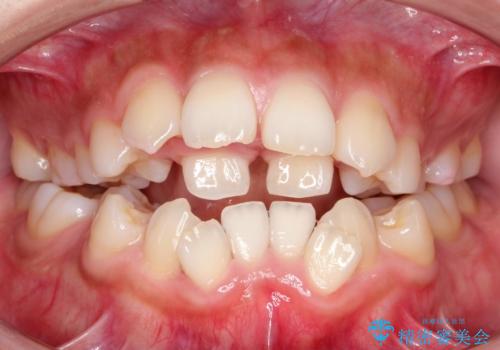

人生が変わる 困難を極める咬合状態に歯列矯正単独で挑戦する

骨格的要因を背景にもつ不正咬合のため、歯列矯正単独での改善は困難と判断しましたが、患者さんとの相談の結果、歯列矯正単独で可能なところまで一緒に頑張りましょうということで、治療をすすめました。

シビアな叢生や開咬も改善することができ、想像以上の改善に時間をかけた甲斐があったと満足していただけました。